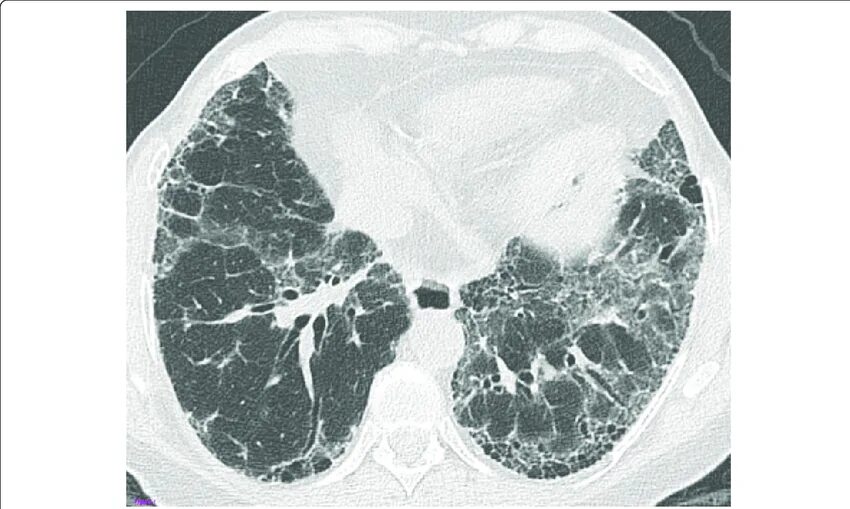

Как лечить пневмофиброз легких у взрослых